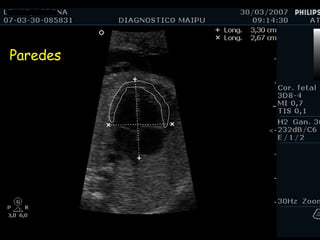

EXAMEN BASICO VENTRICULOS Tamaños Paredes Banda moderadora Tabique

Tamaño

Paredes

Tabique